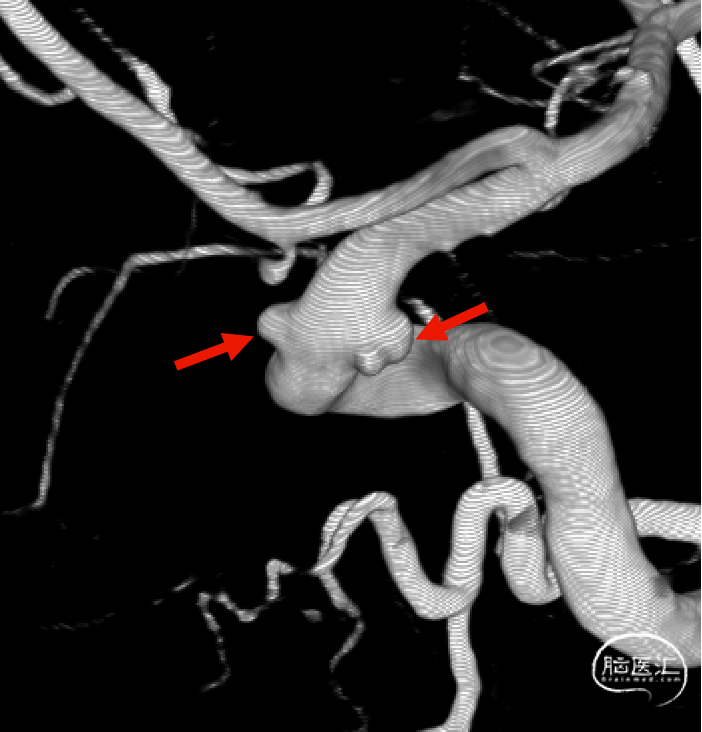

CTA:右侧颈内动脉C6段动脉瘤。

DSA:DSA提示右侧颈内动脉C6段可见多发动脉瘤。

术前诊断:右侧颈内动脉C6段多发动脉瘤。

载瘤动脉远端血管直径:4.0mm

载瘤动脉近端血管直径:4.9mm、4.5mm(两个角度)

密网支架:强易达Choydar血流导向装置 FD475-20

支架到位,远端打开(正侧位):4.75-20mm支架在大脑中动脉M1段打开,回撤至C6段远端锚定。支架释放过程中,轻柔推送支架系统,可见支架导管沿血管壁大弯侧走行,支架打开良好。

术后造影:支架覆盖两枚动脉瘤瘤颈,贴壁良好,瘤体内可见造影剂滞留。